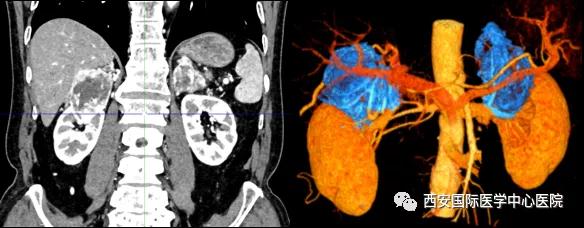

今年七十五歲的患者,來(lái)自陜西省商洛市,四月前因腰背部疼痛就診于當(dāng)?shù)蒯t(yī)院,行CT檢查發(fā)現(xiàn)“右腎、雙側(cè)腎上腺占位,前縱膈淋巴結(jié)腫大,雙肺多發(fā)結(jié)節(jié)、胸椎骨質(zhì)破壞,考慮轉(zhuǎn)移瘤”。為進(jìn)一步診斷治療,患者的兒子帶他來(lái)到西安某三甲醫(yī)院,查泌尿系CT提示“右腎占位性病變,多考慮腎癌,雙側(cè)腎上腺多發(fā)轉(zhuǎn)移灶,腹膜后多發(fā)腫大淋巴結(jié)”;行穿刺活檢提示“腎透明細(xì)胞癌”;并給予患者口服靶向藥物的治療方案。

自四月份至今,患者一直口服靶向藥物治療(阿昔替尼5mg 2次/日),期間無(wú)不良反應(yīng),目前腰背部疼痛癥狀也有所緩解,復(fù)查影像學(xué)資料提示瘤體較前縮小,腫瘤完整切除的可能性明顯提高;而且患者的兒子也是一名外科醫(yī)生,所以他更想為父親完成后續(xù)的手術(shù)治療。

手術(shù)由楊增悅教授主持,舒濤主治醫(yī)師、王東主治醫(yī)師主刀,黃怡醫(yī)師、王平醫(yī)師協(xié)助完成。由于第四代達(dá)芬奇機(jī)器人更加靈活和精準(zhǔn)的特性,手術(shù)全程順利,尤其是完全精準(zhǔn)的“解鎖”了右腎動(dòng)脈和右腎靜脈的數(shù)十根交互纏繞的分支血管。術(shù)后患者麻醉恢復(fù)后生命體征平穩(wěn),順利返回泌尿外科普通病區(qū)進(jìn)一步康復(fù)。